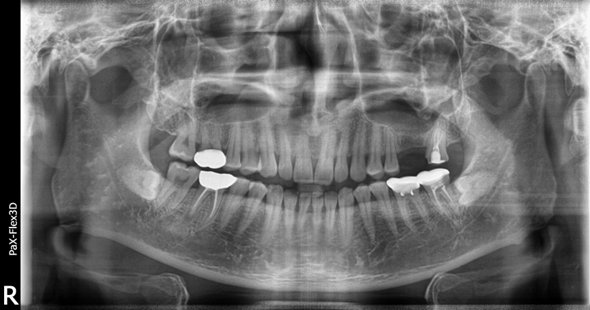

39세 남성

상악동거상술 뼈이식 후 임플란트 식립

(전) 2021-12-07 (후) 2022-08-29

위 어금니 임플란트 진행 시 잇몸뼈가 부족해 광대뼈 안쪽 막을 들어올리고 뼈이식을 진행하는 상악동거상술을 시행한 환자분입니다.

상악의 경우 하악보다 잇몸뼈가 얇아 뼈이식의 난이도가 높고 최종 완료까지 걸리는 시간도 긴 편입니다.

따라서 성공적인 케이스를 많이 다뤄본 의사에게 시술받는 것이 좋은 결과를 가져올 수 있는 지름길입니다.

68세 남성

보험임플란트

(전) 2021-11-05 (후) 2022-08-18

만 65세 이상으로 국가에서 금액을 일부 지원하는 보험임플란트를 진행하신 환자분입니다.

치아가 상당 부분 결손되어 있어 생활하시는데 불편함이 많으셨을텐데, 임플란트 시술 후 씹는 즐거움을 되찾을 수 있었습니다.

상실된 치아를 방치하게 되면 치아가 조금씩 이동해 치아 배열이 망가지고 임플란트 식립이 어려워질 수도 있습니다.

따라서 빠르게 치과에 방문하셔서 치료받으시는 것이 가장 좋습니다.